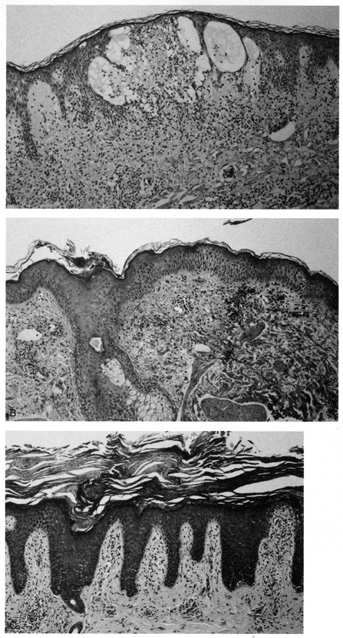

All types of dermatitis are characterized histologically by spongiosis (accumulation of fluid between the keratinocytes of the epidermis) and a mild, superficial perivascular, predominantly lymphohistiocytic, mononuclear cell infiltrate in the superficial dermis. Confluent spongiosis leads to intraepidermal vesiculation in acute dermatitis (Fig. 3A), and milder or focal spongiosis without vesiculation is seen in subacute variants (see Fig. 3B). Chronic dermatitis is characterized by compact orthokeratosis (usually secondary to the patient rubbing), irregular epidermal hyperplasia, and scant to absent spongiosis. In the superficial dermis (papillary dermis), the collagen bundles are abnormally thickened and are oriented perpendicular to the plane of the epidermis (see Fig. 3C).

Fig. 3. A. Acute dermatitis with confluent intraepidermal spongiosis leading to vesicle formation. B. Subacute dermatitis with moderate intercellular edema (spongiosis). C. Chronic dermatitis with lichen simplex chronicus (compact orthokeratosis, irregular epidermal hyperplasia, and papillary dermal fibrosis).